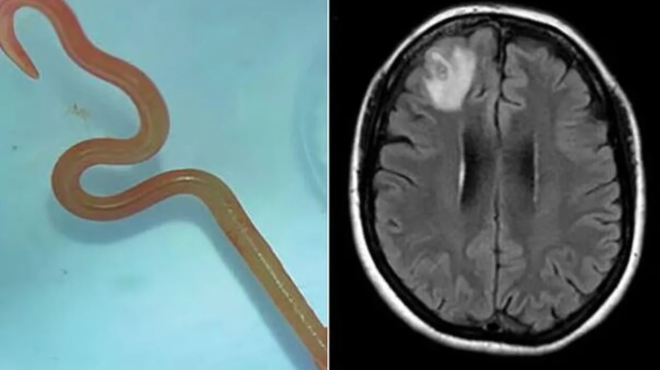

Μέχρι το 2022, τα συμπτώματά της περιελάμβαναν επίσης απώλεια μνήμης και κατάθλιψη, με αποτέλεσμα να διακομισθεί σε νοσοκομείο της Καμπέρα και μια μαγνητική τομογραφία του εγκεφάλου της αποκάλυψε ανωμαλίες που απαιτούσαν χειρουργική επέμβαση.

«Αλλά ο νευροχειρουργός σίγουρα δεν μπήκε εκεί μέσα πιστεύοντας ότι θα βρει ένα σκουλήκι που σπαρταράει», υπογράμμισε, όπως αναφέρει στον Guardian, ο Δρ. Sanjaya Senanayake του νοσοκομείου της Καμπέρα και προσθέτει «οι νευροχειρουργοί ασχολούνται τακτικά με λοιμώξεις στον εγκέφαλο, αλλά αυτό ήταν ένα εύρημα που βλέπουν πρώτη φορά στην καριέρα τους. Κανείς δεν περίμενε να το βρει αυτό».

«Η Καμπέρα είναι ένα μικρό μέρος, οπότε στείλαμε το σκουλήκι, το οποίο ήταν ακόμη ζωντανό, κατευθείαν στο εργαστήριο ενός επιστήμονα του CSIRO, ο οποίος έχει μεγάλη εμπειρία με τα παράσιτα», σημείωσε ο Senanayake και συμπλήρωσε «απλώς το κοίταξε και είπε: ‘Θεέ μου, αυτό είναι το Ophidascaris robertsi’».

Το Ophidascaris robertsi είναι ένα στρογγυλό σκουλήκι που συναντάται συνήθως στους πύθωνες και η ασθενής του νοσοκομείου της Καμπέρα είναι η πρώτη περίπτωση παγκοσμίως που το παράσιτο βρέθηκε σε άνθρωπο.